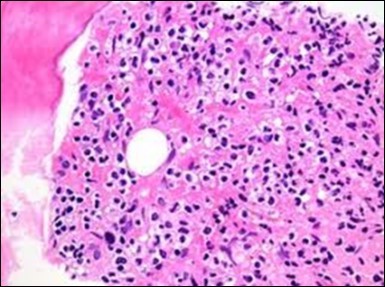

The leukaemia cells may enunciate a characteristic immune phenotype, crucial for a confirmatory diagnosis. The peripheral blood mononuclear B cell population may display a kappa or lambda light chain restriction. The phenotype of classic hairy cell leukaemia may be delineated by concurrent, immune reactive CD19+ CD20+,CD 11c+, CD25+, CD103+ and CD123+. An intensely immune reactive CD200+ and a non reactive CD27- antigen may be present2, 4. Evaluation of a trephine bone marrow biopsy and bone marrow aspirate may define the degree of tumour infiltration. A dry tap on account of prominent bone marrow fibrosis may be elucidated at preliminary diagnosis. A decline in the normal haematopoiesis may account for a hypo-cellular marrow in 10% instances. Gradation of cellular infiltrating of the leukaemia within the bone marrow may be appropriately investigated with immune –histochemical stains2, 4. Immune staining for CD20+, annexin 1 and VE1 (a BRAF V600E stain] may validate the diagnosis and precisely analyse the extent of malignant bone marrow infiltration[8]. Determination of BRAF V600E mutation may be critical in therapeutically non responsive individuals with applicable standard therapy or in instances of multitudinous reoccurrences[9]. Deploying inhibitors of BRAF V600E gene may be efficacious in patients impervious to approved therapy. The mutation necessitates a comprehensive scrutiny of the implicated individuals with a sensitive molecular assay which may discern up to < 10% of the hairy leukaemia cells appearing in the peripheral blood smears or bone marrow aspirates diluted with peripheral blood or aspirates elucidating a dry tap[2,4]. Allele specific polymerase chain reaction (PCR) or a next generation sequencing may be optimally employed to circumvent false negative outcomes. If the leukaemia cells are sparse or if particularly sensitive & efficacious molecular techniques are not accessible, the application of appropriate immune histochemical stains to the bone marrow biopsy such as a BRAF V600E mutation stain (VE1) may detect the hairy cells and conclusively diagnose the condition[2,4,10]. Figure 1, Figure 2, Figure 3, Figure 4, Figure 5, Figure 6, Figure 7, Figure 8, Figure 9, Figure 10, Figure 11, Figure 12, Figure 13, Figure 14.

Figure 5.HCL: hairy cells with infiltration in the spleen(21).

Figure 6.HCL: disseminated hairy cells with a clear cytoplasm(22).

Figure 7.HCL: blebs on the cellular surface with fine nuclear chromatin(23).